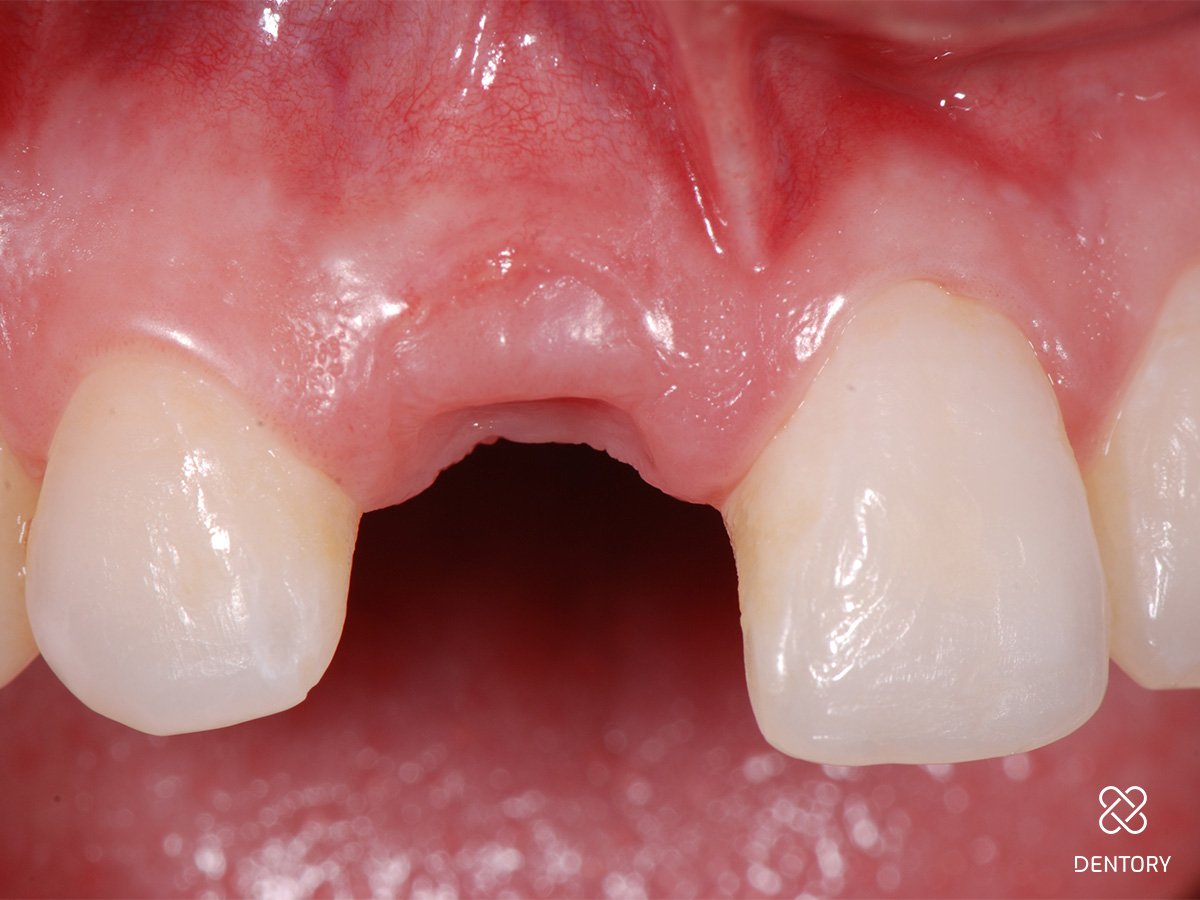

Abbildung 5

Sondieren der bukkalen Knochenstrukturen mittels Biotyp-Sonde; im Bereich der Resorption kam es zum lokalen Verlust der vestibulären Lamelle.